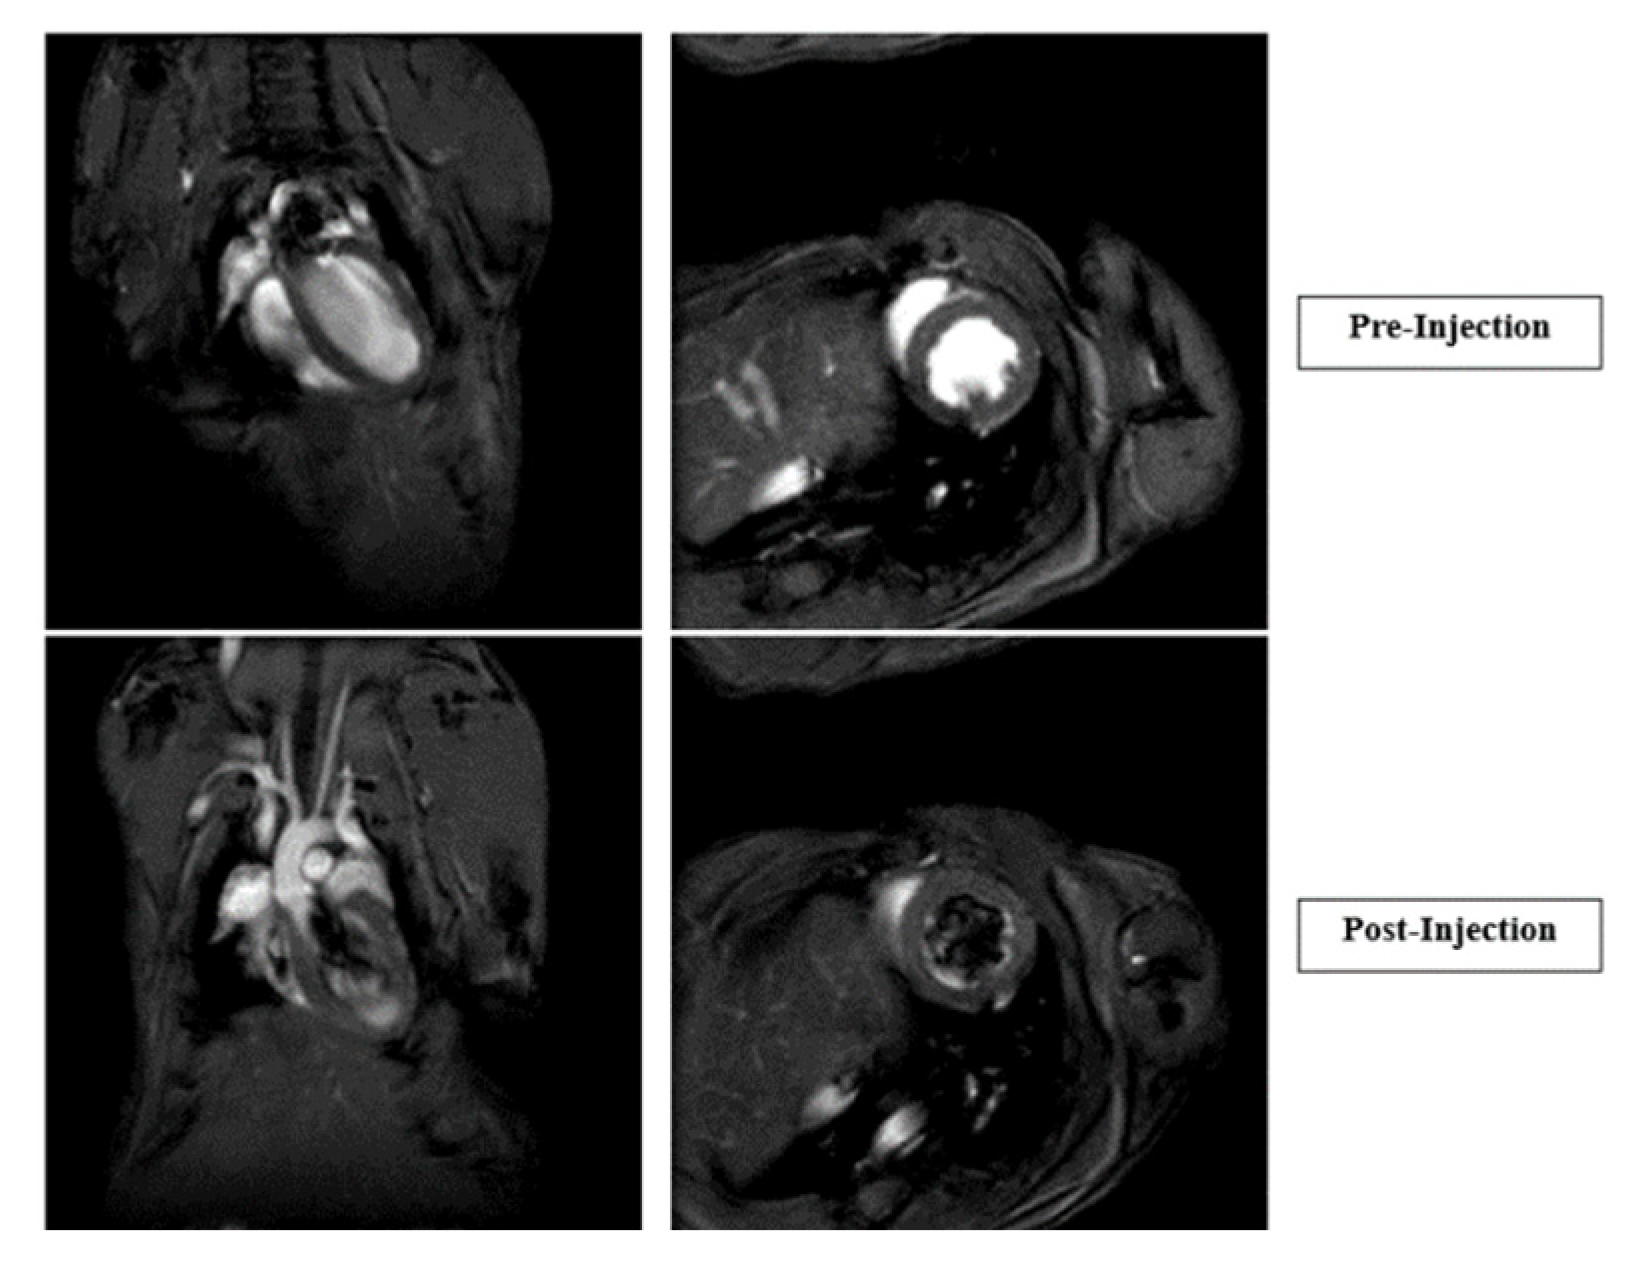

Cardiac Function Studies, Pre- and Post-Injections: Six CD1, wild type, 6–8-week-old adult mice were obtained from the Charles River and used for cardiac MRI studies. Mice were weighed, anesthetized with 2.5% isoflurane, and ear tags removed before being inserted into the MRI scanner. A baseline cardiac MRI was performed, followed by intravenous CTP injection (150 µg/Kg). Post-injection, a second cardiac MRI was performed.

Cardiac MRI showed no significant change in heart rate, left ventricular mass, ejection fraction, or cardiac output post-CTP injection in male or female mice (Figure 7).

Figure 7.

Cardiac MRIs of pre- and post-injection of CTP. Graphs showing heart rate, left ventricular (LV) wall mass, and 2D and 3D cardiac output immediately after CTP injection.